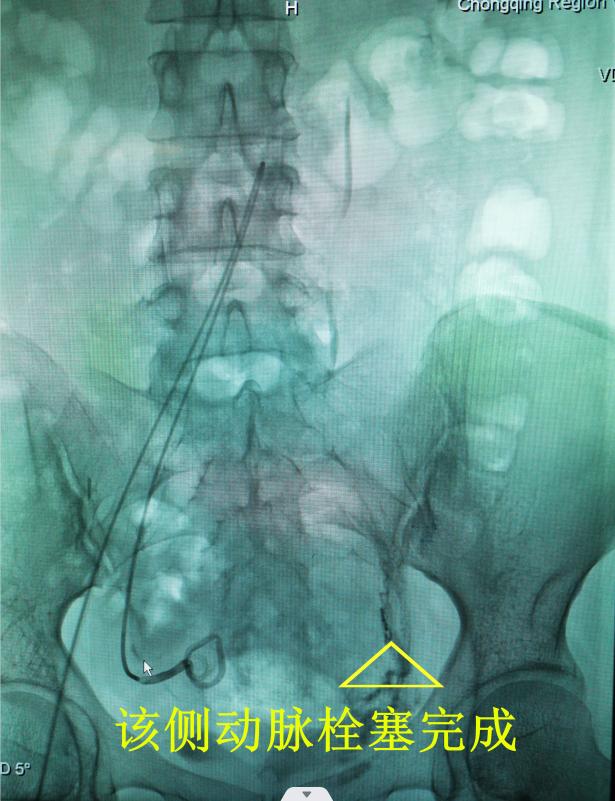

子宫动脉栓塞术是介入手术的一种,是通过股动脉置入导管,在X线指引下进入子宫动脉,用栓塞剂堵住动脉血管,避免手术时大量出血,这是一项4级手术,对医生团队和技术设备要求高。

经充分的术前讨论和准备,李春梅副主任医师带领团队首先为黎女士成功完成了“双侧子宫动脉栓塞术”,推回病房休息并观察评估,15小时后又顺利完成了“腹腔镜下剖宫产瘢痕妊娠病灶清除术+腹腔镜子宫下段修补术+子宫肌瘤剜除术+双侧输卵管结扎+肠粘连松解术+盆腔粘连松解术”6项手术及膀胱灌注。 术中出血仅50ml,生命体征平稳,返回病房,两日后康复出院。